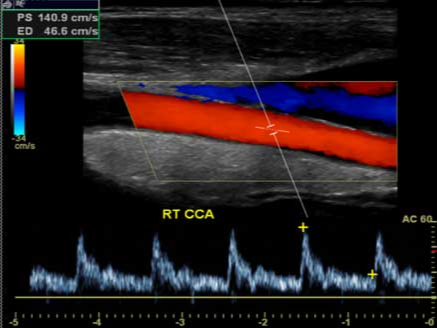

경동맥 초음파(Carotid Doppler ultrasound)는 초음파를 이용해 목 부위에 위치한 경동맥의 혈류 흐름과 혈관 구조를 영상으로 확인하는 검사입니다.

- 원리: 초음파 탐촉자가 혈관 위를 스캔하면서 반사파(Doppler effect)를 분석해 혈류 속도와 방향, 혈관 벽 구조를 실시간으로 파악합니다.

- 동맥벽 두께, 플라크(plaque) 유무, 혈류 속도 측정